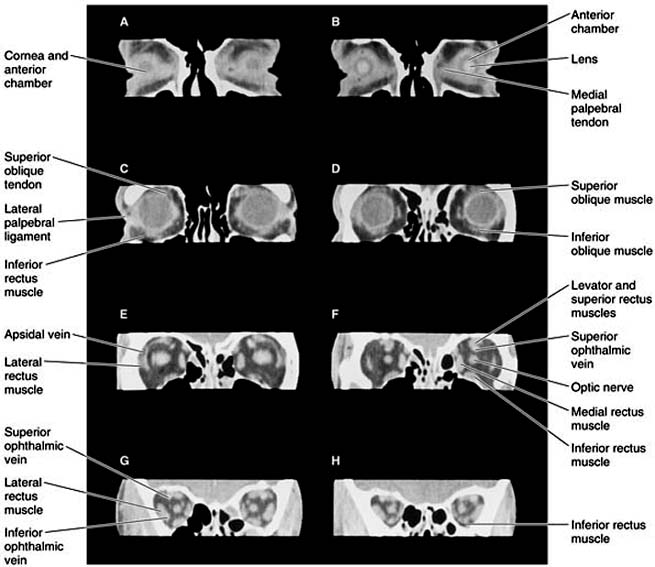

Figure 13-1

Figure 13-1: Normal CT scan showing the anatomy of the orbit. Axial CT sections, thickness 1.5 mm. A: Lowest section. H: Highest section. Note clear delineation of individual muscles, optic nerve, and major veins within the orbital fat.